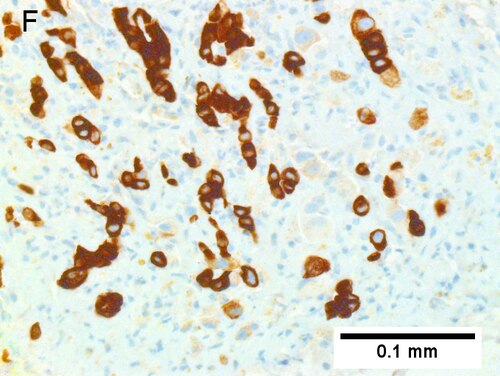

Cholangiocarcinoma, intrahepatic, large duct type. Extremely unfortunate case arising in a pre-teenage girl. A. MRI showing multiple hepatic masses. B. A mass comprising often large ducts abuts uninvolved liver. C. CK7 immunostain emphasizes large, often adjoining ducts. D. Trichrome stain shows spread of tumor into scar with collagen deposition. E. Reticulin stain emphasizes disorderly vertical and horizontal spread of bizarrely shaped acini. F. PAS-D stain shows luminal mucin; note absence of red lining of outside of ducts seen in normal bile ducts/proliferating bile ductules. G. Loss of polarity (varied orientation with respect to base of epithelium) and variable size and shape of nuclei are obvious (Row 3 Right 400X, high pixel image). | |||

Cholangiocarcinoma, intrahepatic, large duct type. Extremely unfortunate case arising in a pre-teenage girl. A. MRI showing multiple hepatic masses. B. A mass comprising often large ducts abuts uninvolved liver. C. CK7 immunostain emphasizes large, often adjoining ducts. D. Trichrome stain shows spread of tumor into scar with collagen deposition. E. Reticulin stain emphasizes disorderly vertical and horizontal spread of bizarrely shaped acini. F. PAS-D stain shows luminal mucin; note absence of red lining of outside of ducts seen in normal bile ducts/proliferating bile ductules. G. Loss of polarity (varied orientation with respect to base of epithelium) and variable size and shape of nuclei are obvious (Row 3 Right 400X, high pixel image).